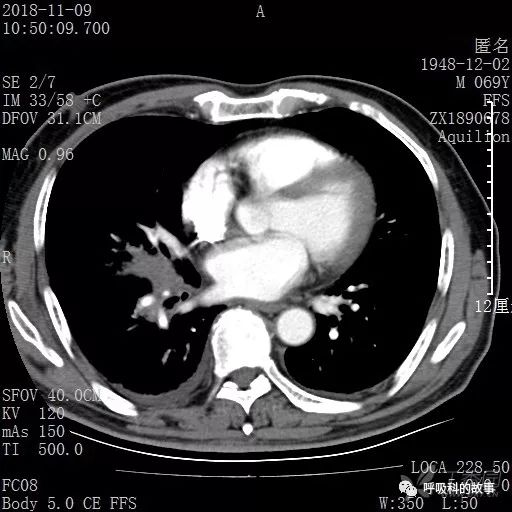

胸部增强CT示右肺门占位伴远端阻塞性肺炎,纵膈、右肺门、右侧颈根部、右侧腋下及肝门部肿大淋巴结。两侧胸腔少量积液。

纵隔窗的增强CT